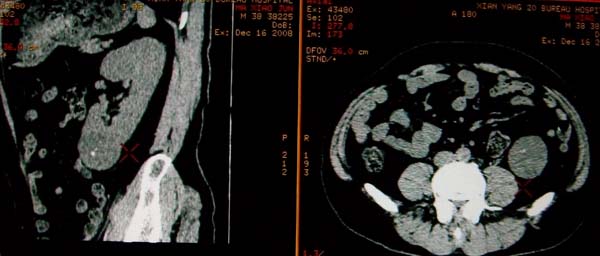

标题: CT17174:M38Y,体检超声提示右肾发育不良,病人无明显不适 [打印本页]

标题: CT17174:M38Y,体检超声提示右肾发育不良,病人无明显不适

1)左肾下极占位性病变,不排除肾癌可能;建议行进一步检查。2)右肾发育不良。

左肾下极占位性病变,不排除肾癌可能;建议增强及明确内部组织ct值。右肾发育不良。

右肾发育不良。左肾代偿。左肾下极占位,性质待定,建议强化。

右肾发育不良。左肾下极占位。建议增强!

右肾发育不良。左肾下极囊实性占位,建议增强。